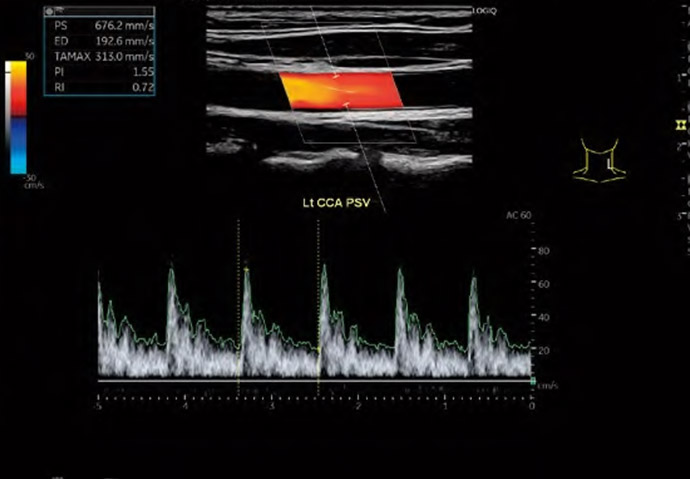

当院では頸動脈エコーを行い、動脈硬化の程度やプラーク*のチェックを行います。

*『プラーク』とは、血管壁が限局性に盛り上がってできた隆起性病変で、脳梗塞などのリスク因子と考えられます。